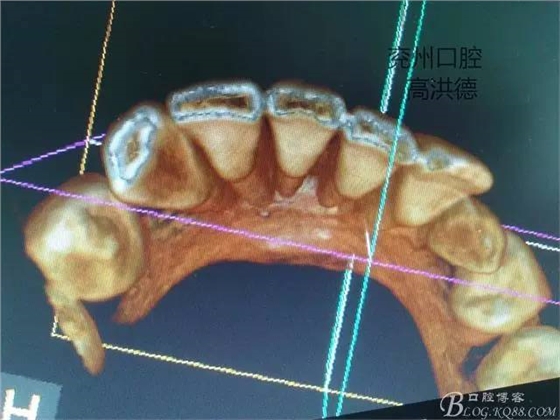

冠狀位,舌側(cè)觀